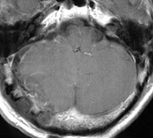

以下の画像に呈示するような脳幹や小脳を圧迫する大きい腫瘍に対しては、開頭手術が優先されます。手術中に神経刺激装置・聴性脳幹反応など電気生理学的モニタリングを併用し、1つ1つの手術操作によって神経機能を損傷していないか随時チェックしながら手術を行っており、術後後遺症の予防に努めています。